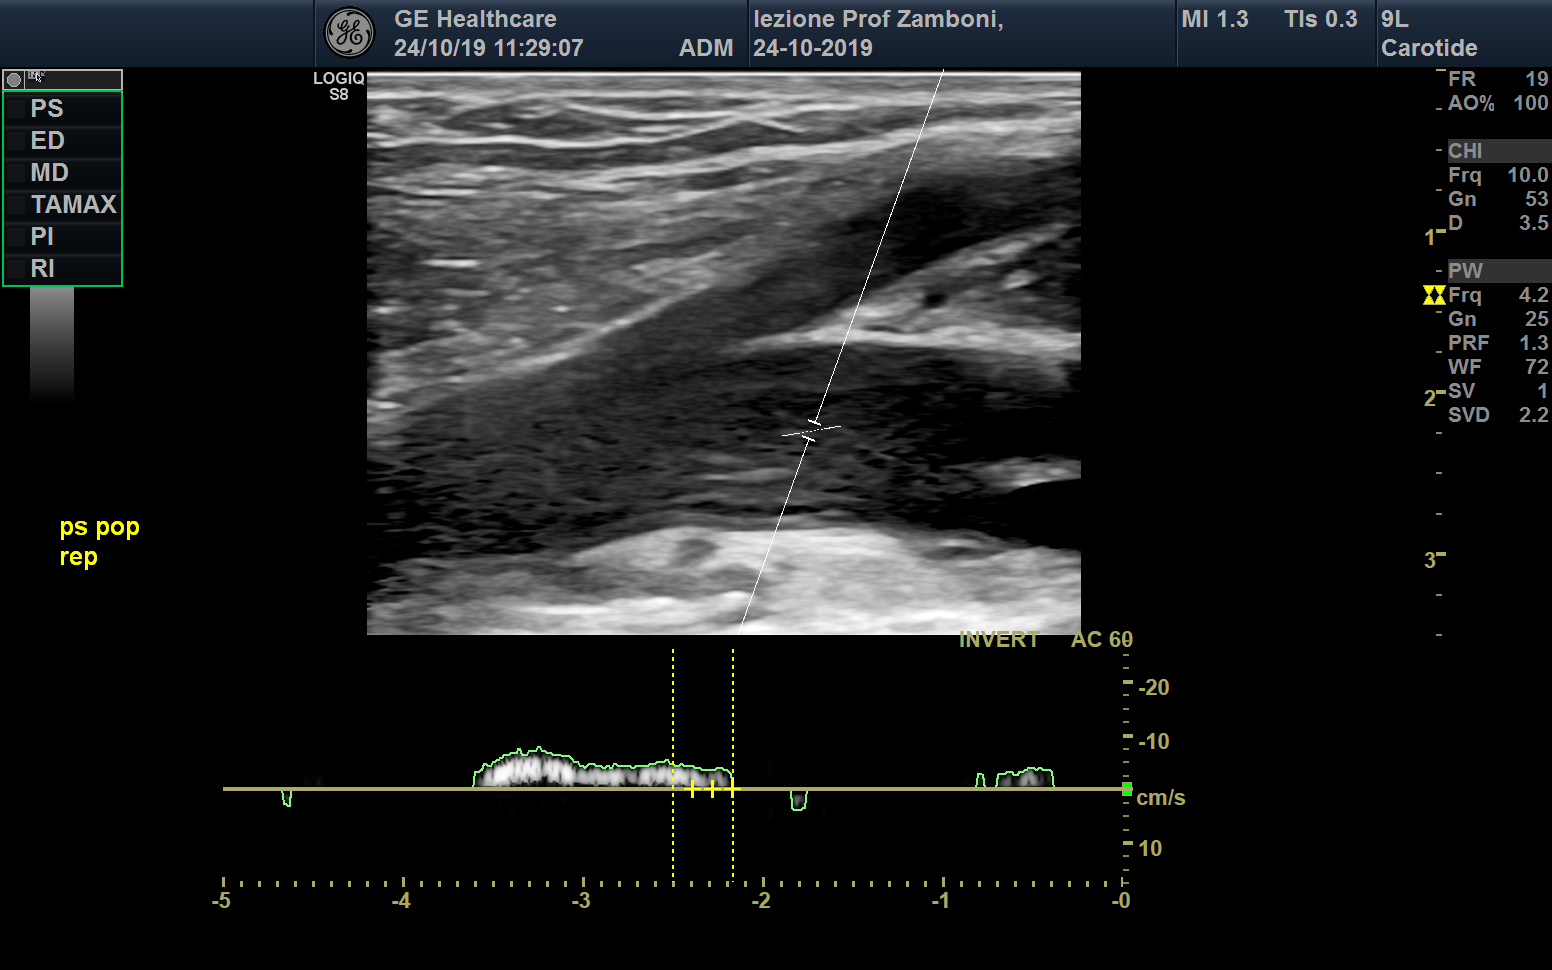

PW V. Poplitea respiro

JPEG image icon PW V. Poplitea respiro.jpg — JPEG image, 484 kB (496043 bytes)